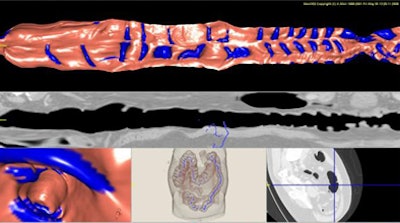

The haustral fold detection method employs a ridge structure enhancement filter based on eigenvalues of a Hessian matrix, Oda explained. First, it assesses the approximate distribution of CT values in the image data by fitting a quadratic polynomial equation at three data points for each voxel, each representing a local cubic region.

A Hessian matrix is then calculated using second-order partial differential coefficients of the fitted surface. The output of a ridge structure enhancement (RSE) filter is then calculated from the eigenvalues of each voxel, and the output is used to generate an enhanced image of haustral fold regions.

![]() |

| The proposed haustral fold detection method employs an RSE filter calculated from the eigenvalues of each voxel, using the output to generate an enhanced image of the haustral fold regions. All images courtesy of Masahiro Oda. |

False positives are reduced by eliminating the smallest voxels, eliminating the smallest connected regions, and eliminating the connected regions with the lowest connectedness values, Oda said. The remaining output is then classified into haustral fold regions.

Once the folds are detected in both prone and supine data, the folds are numbered and used to manually generate supine and prone correspondence of VC data, he said.

Oda and his team applied their method to MDCT virtual colonoscopy data from 12 patients. Three-dimensional CT datasets, acquired using a 512 x 512-pixel image matrix, collimation of 1.25 mm, and slice thickness of 0.6-0.7 mm, were analyzed for the study.

Except for the smallest structures, nearly all of the haustral folds were detected, "including 81.7% (1,326/1,624) of haustral folds, with 6.9 false positives per case," Oda said. "Sensitivity was higher than a previous method," he said.

| The results show detected haustral folds marked in blue. |